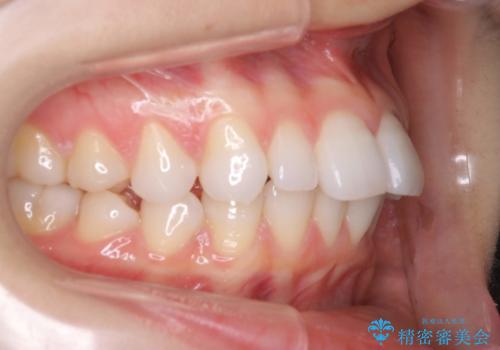

インビザラインで出っ歯を改善する 抜歯をしないinvisalign治療

- 非抜歯・遠心移動による前突の改善をマウスピースにて計画した。

非抜歯矯正の場合、大きく前歯を下げることはできませんが、奥歯の遠心移動や歯のサイズダウンにより歯軸を立て、見かけ上の出っ歯感をある程度改善することができます。